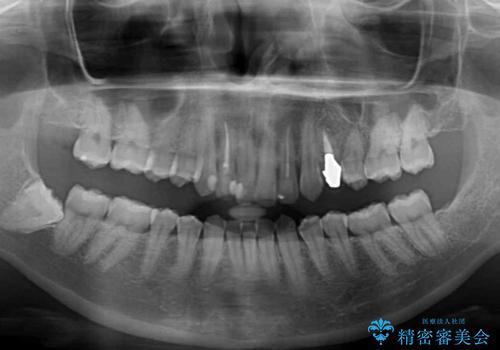

- 前歯の歯並びと神経を取って変色してしまった前歯を気にして来院された患者様です。

上下前歯の歯列不正はインビザラインにより整え、その後に、前歯2本をオールセラミッククラウンにて補綴治療することとしました。

下顎前歯が1本欠損しており、下顎歯列の大きさが本来よりも小さいため、上顎歯列とのバランスが悪く、深い咬み合わせになっていました。

上顎にIPRを多用して歯列の大きさを小さくするよう試みましたが、理想的な咬み合わせまでには改善させることはできませんでした。